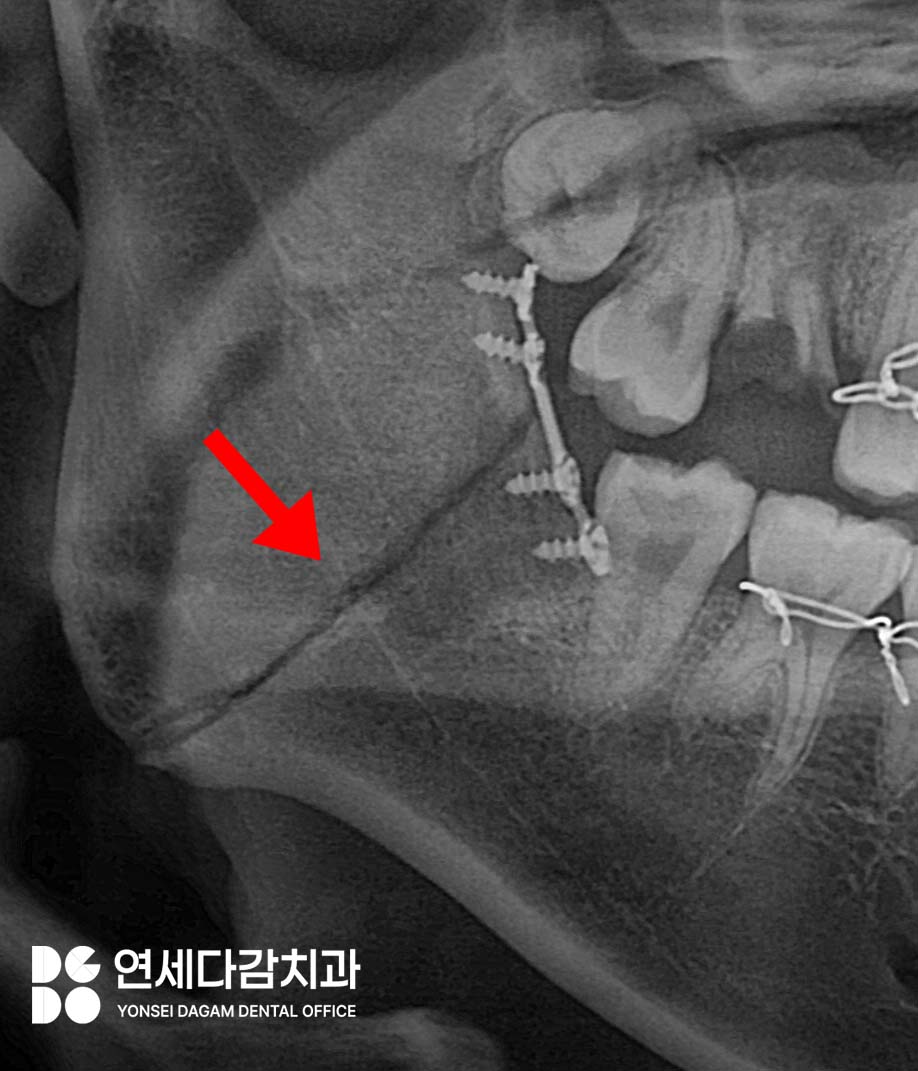

사고 시 해부학적으로 부러지기 쉬운

부위가 있습니다.

하악각 부위, 하악 정중부,

하악과두 부위가 대표적인

골절 호발 부위입니다.

관절 부위가 다친다면

더 심각한 상황이 될 겁니다..

턱뼈가 골절됐을 때는 3차병원에서

턱뼈 골절수술과

악간 고정을 시행하게 됩니다.

나사와 metal plate를 이용해

부러진 뼈를 올바른 위치에 고정하고

골절이 치유되도록 하고,